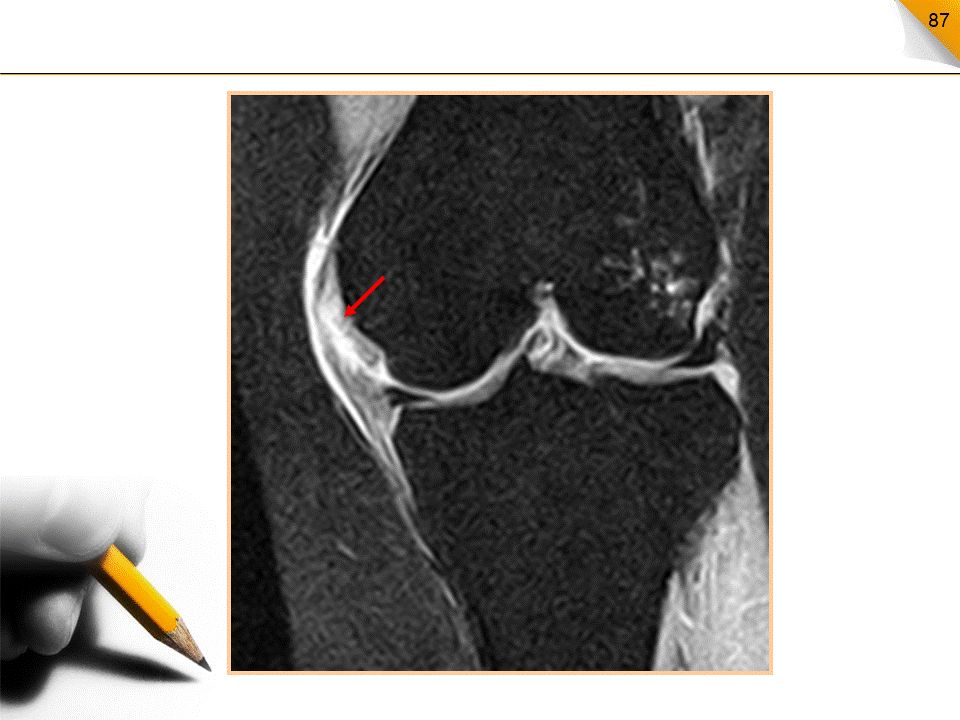

前交叉韧带撕裂MR表现

部分撕裂:局部信号增高、边缘毛糙松弛扭曲完全撕裂:连续性中断,断端毛糙呈拖把状急性撕裂:伴有关节腔积液和髌下脂肪垫水肿

前交叉韧带完全撕裂直接征象:连续性中断、韧带增粗、信号增高间接征象:PCL曲度异常、胫骨前移、股骨髁和胫骨平台的骨挫伤、半月板及侧副韧带撕裂等。